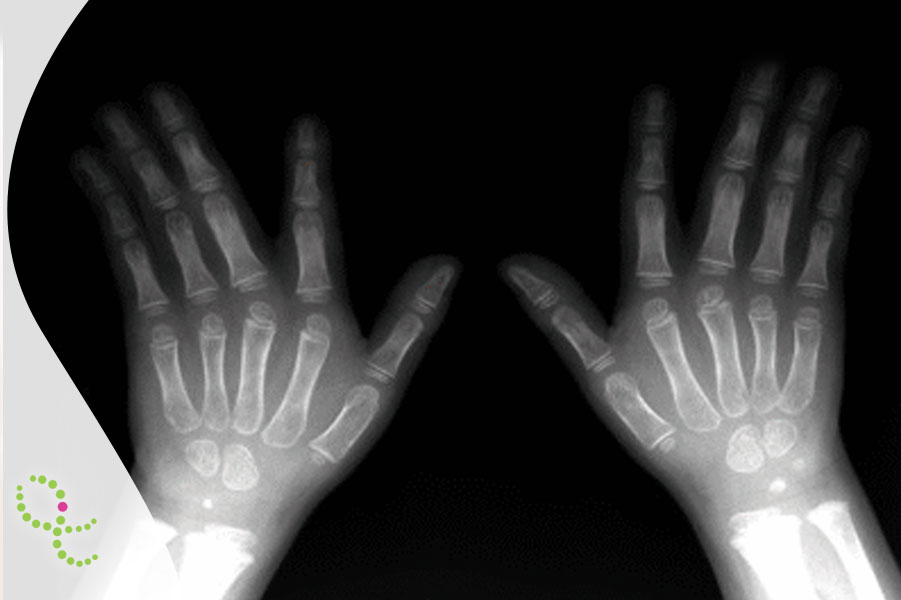

De origem genética: 80% são causadas por fatores ligados à genética do paciente. Alguns exemplos são erros inatos do metabolismo (distúrbios que, em geral, se relacionam à produção de enzimas no organismo que não conseguem quebrar, armazenar ou transportar as moléculas no organismo) e anomalias congênitas ou de manifestação tardia (alterações que podem ocorrer durante o desenvolvimento do embrião que geram deformações estéticas ou afetam até mesmo as funções de alguns órgãos/sistemas.